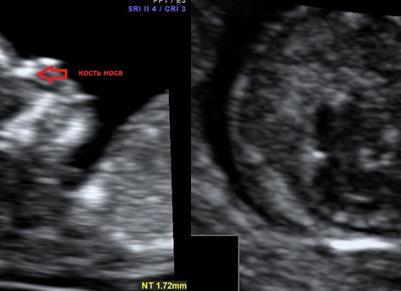

Носовая кость плода на УЗИ

Длина кости носа у эмбриона – один из важнейших показателей правильного развития плода. Если носовая кость на УЗИ имеет размер меньше нормы, можно говорить о таком явлении, как гипоплазия носовой кости у плода.

Нормы размеров

Гипоплазия носа выявляется при сравнении длины кости носа эмбриона на УЗИ с аналогичным усредненным значением здоровых детей. Однозначным признаком нарушения является аплазия – полное отсутствие носовой кости, но и уменьшение длины костной части носа тоже может свидетельствовать лишь о вероятных патологиях.

Учитывая тот факт, что показатель может незначительно отличаться из-за индивидуальных особенностей (размера эмбриона, точного срока беременности), диагноз ставится в том случае, если показатель ниже минимального допустимого порога.

| Возраст эмбриона (недели) | Диапазон допустимых значений (мм) | Средний показатель (мм) |

| 12 – 13 | 2,0 – 4,2 | 3,1 |

| 14 – 15 | 2,9 – 4,7 | 3,8 |

| 16 – 17 | 3,6 – 7,2 | 5,4 |

| 18 – 19 | 5,2 – 8,0 | 6,6 |

| 20 – 21 | 5,7 – 8,3 | 7,0 |

| 22 – 23 | 6,0 – 9,2 | 7,6 |

| 24 – 25 | 6,9 – 10,1 | 8,5 |

| 26 – 27 | 7,5 – 11,3 | 9,4 |

| 28 – 29 | 8,4 – 13,4 | 10,9 |

| 30 – 31 | 8,7 – 13,7 | 11,2 |

| 32 – 33 | 8,9 – 13,9 | 11,4 |

| 34 – 35 | 9,0 – 15,6 | 12,3 |

Важно понимать, что точность исследования зависит от нескольких факторов. Например, от квалификации врача, выполняющего УЗИ, и оборудования, на котором он работает. Риск ложного заключения есть при проведении любого медицинского исследования, поэтому в случае отрицательного результата проводится не менее одной повторной диагностической процедуры.